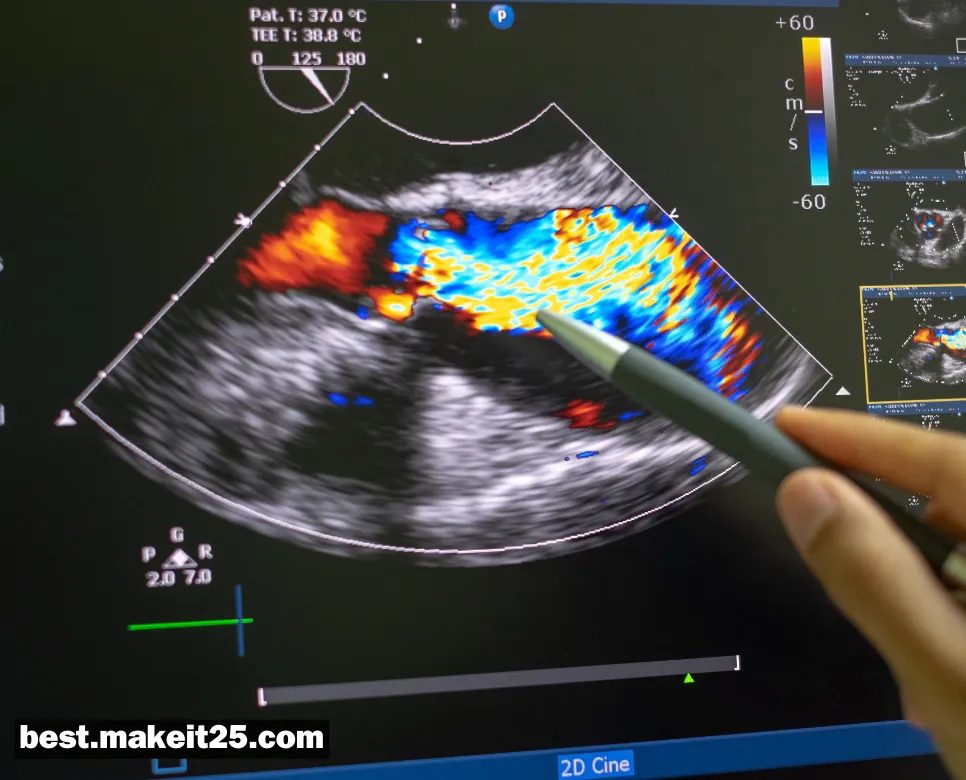

ECHO(심초음파 검사)

의학 용어 ECHO는 “Echocardiography”의 줄임말로, 심초음파 검사를 의미합니다. 심초음파 검사는 초음파를 이용하여 심장의 구조와 기능을 평가하는 비침습적 영상 검사법입니다. 심장의 크기, 심실 및 심방의 기능, 판막 상태, 심낭 질환 등 다양한 심장 질환을 진단하고 평가하는 데 널리 사용되고 있습니다.

심초음파 검사는 다음과 같이 분류할 수 있습니다:

- 경흉부 심초음파: 흉벽에 탐촉자를 대고 시행하는 가장 일반적인 방법으로, 심장의 전반적인 구조와 기능을 평가합니다.

- 경식도 심초음파: 식도 내로 탐촉자를 삽입하여 시행하는 방법으로, 심방, 판막, 대동맥 등 심장 후방 구조물을 더 자세히 관찰할 수 있습니다.

- 부하 심초음파: 운동이나 약물 부하를 가하면서 심초음파를 시행하여 심장의 예비력과 허혈성 변화를 평가합니다.

- 3D 심초음파: 3차원 영상을 획득하여 심장 구조를 입체적으로 분석할 수 있는 최신 기법입니다.